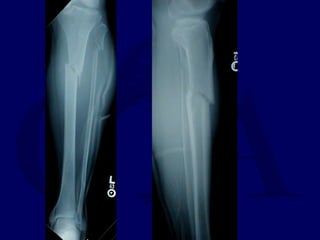

Radiographic Evaluation

• AP and Lat views of entire tib/fib required

from knee to ankle

• Oblique views can be helpful in follow-up

Radiographic Evaluation • APand Lat views of entire tib/fib required from knee to ankle • Oblique views can be helpful in follow-up to assess healing